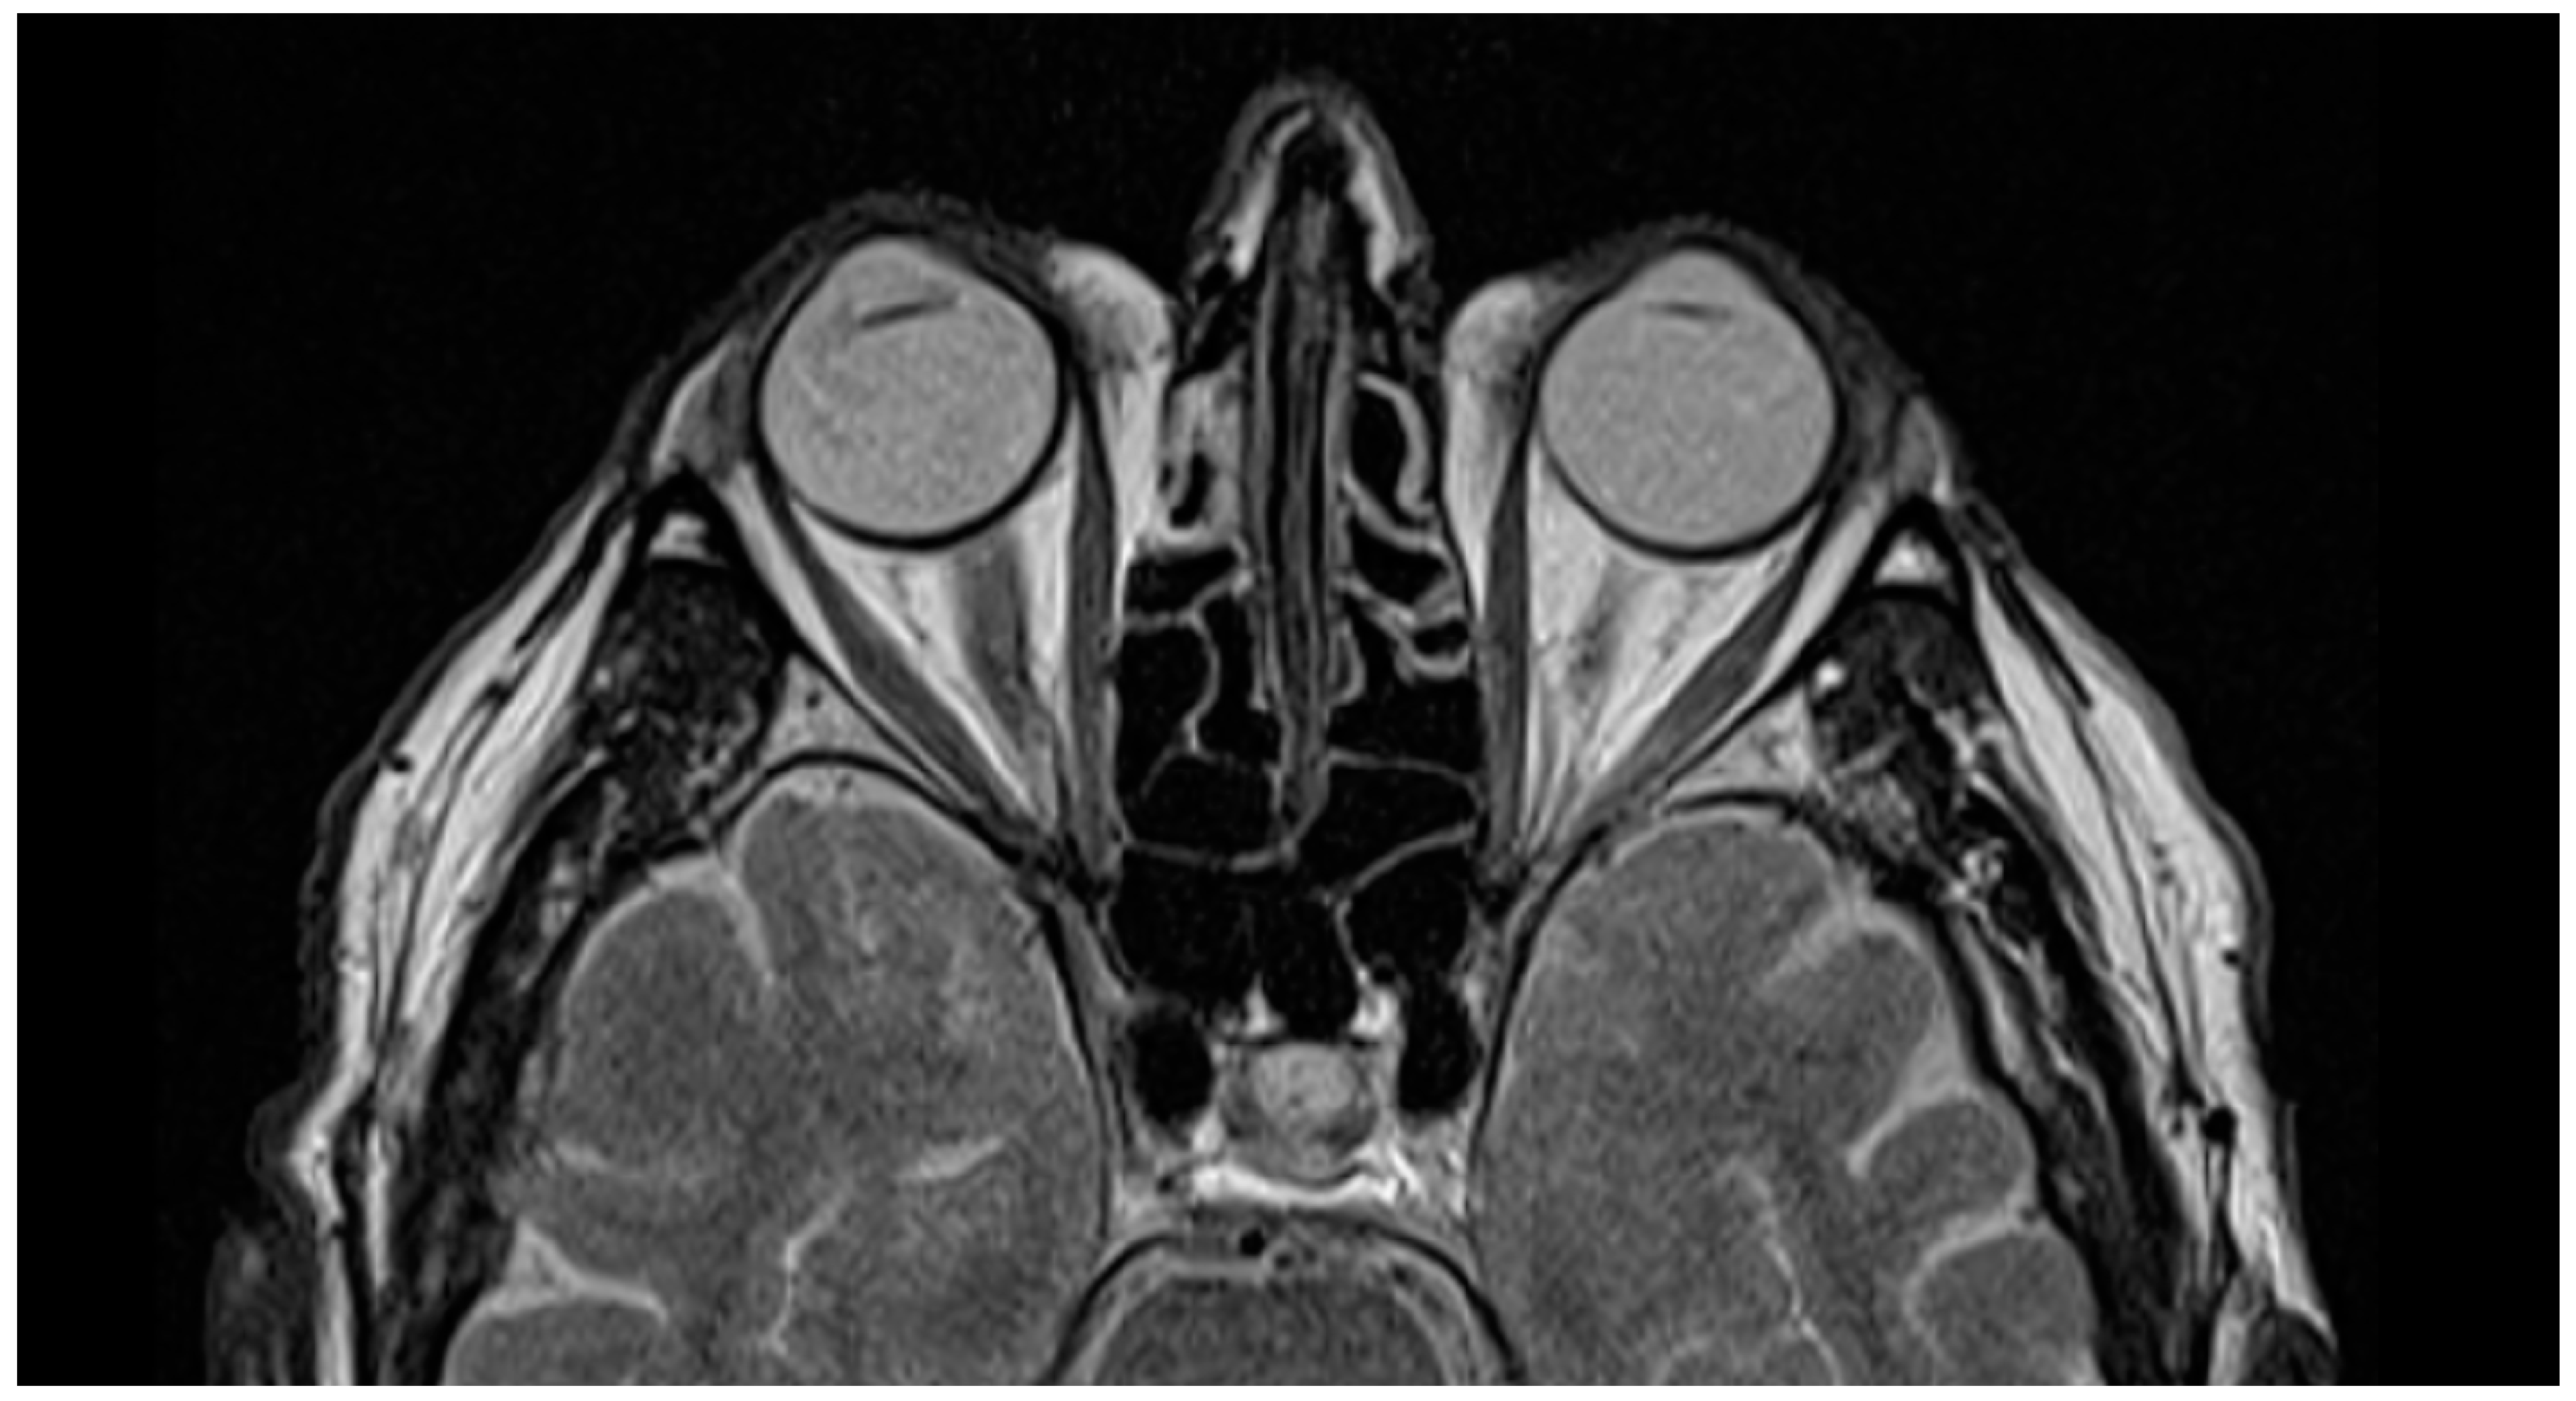

The first patient also underwent magnetic resonance imaging (MRI), which showed the postoperative state of the VaMa and IOL implanted in the eye (Figure 5), where the left eye with the natural lens cannot be clearly distinguished from the right eye with the complex VaMa artificial capsule and IOL. This position of the IOL in aphakic eyes is closest to the physiological one.

Figure 5. MRI shows the VaMa implanted in the right eye of the first patient.